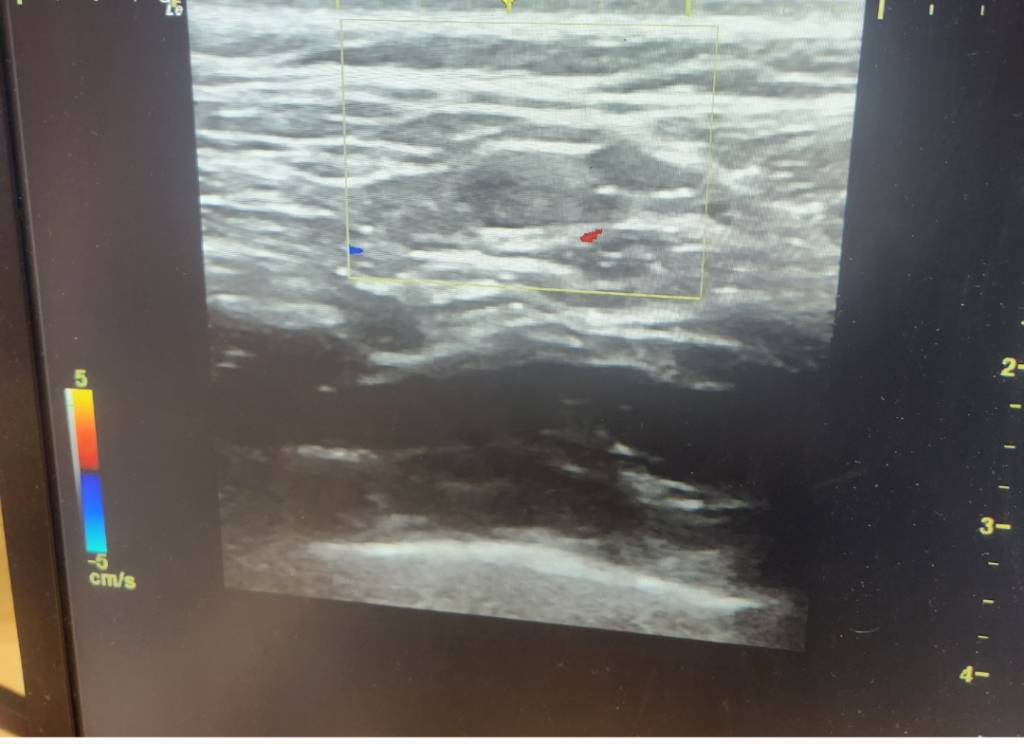

초음파는 직접 시행한 시술자가 가장 잘 압니다.

초음파는 실시간 영상을 보는 것인데 사진 한 장으로 알 수 없습니다.

초음파 만으로 확실한 진단을 내릴수는 없기 때문에 혹의 크기변화 등이 있을 경우 MRI촬영 및 조직검사 까지 진행을 해보시는 것을 추천드립니다.